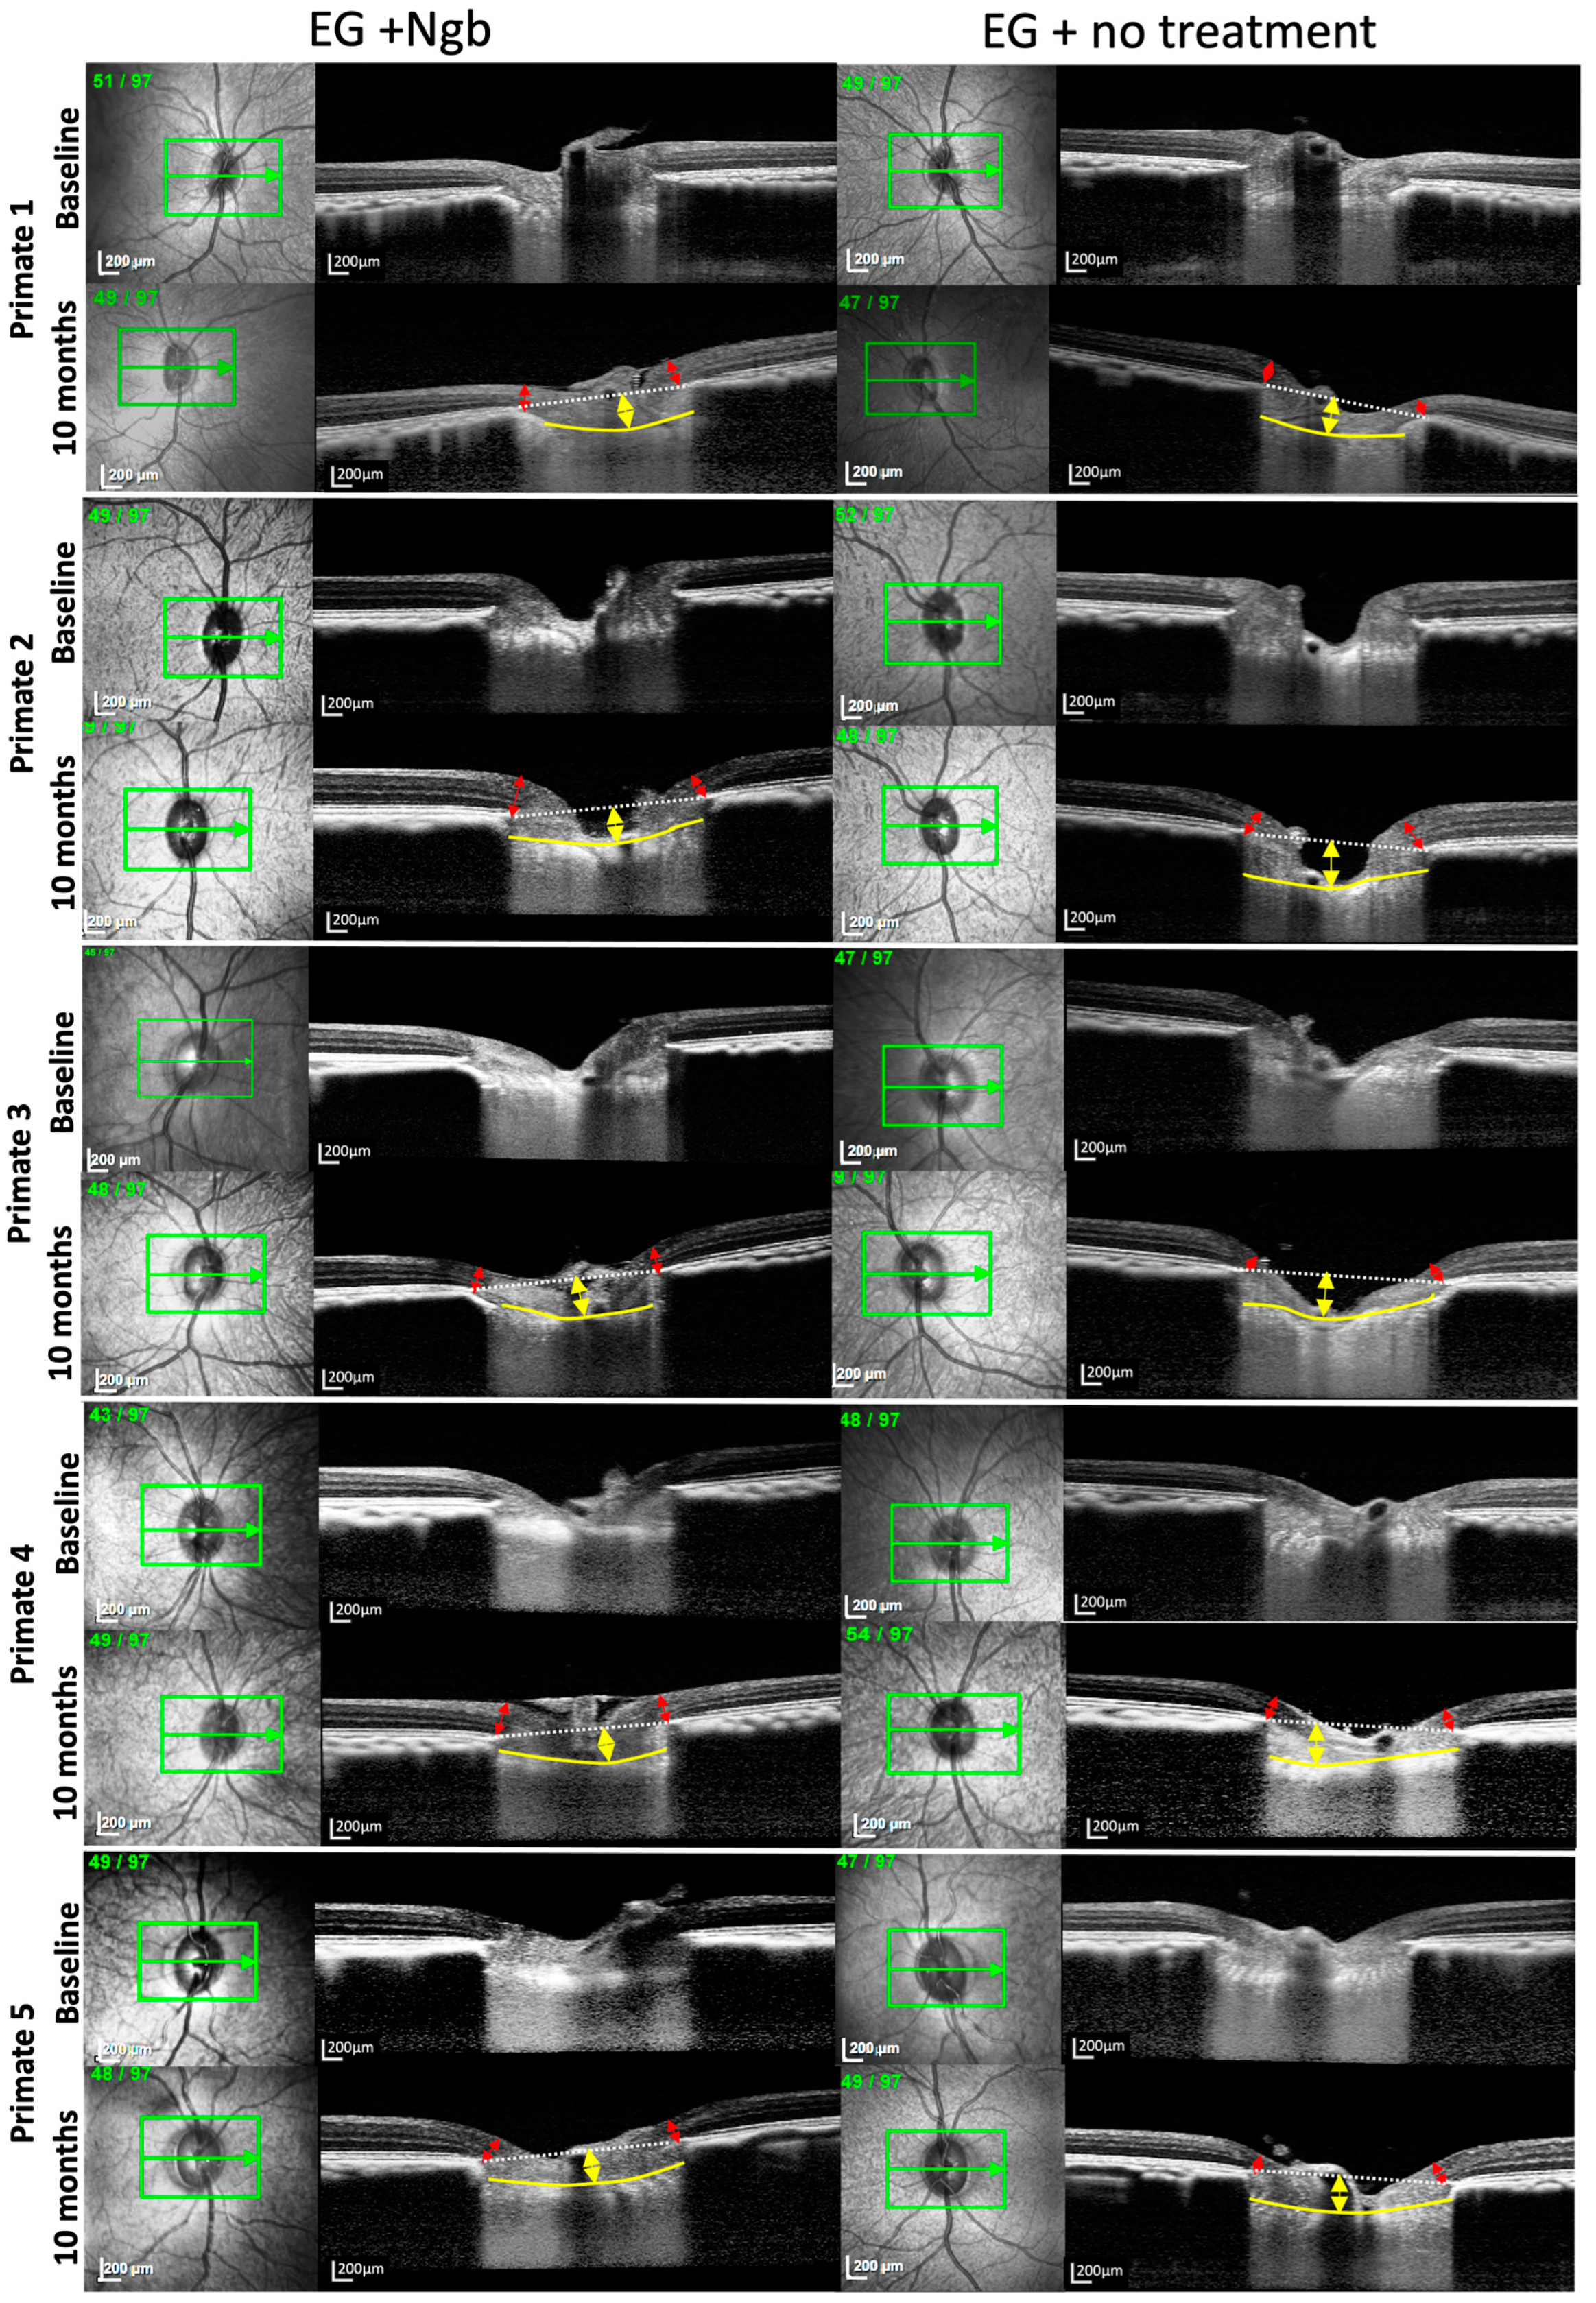

3.3. OCT Structural Changes with EG: Before and after Intervention